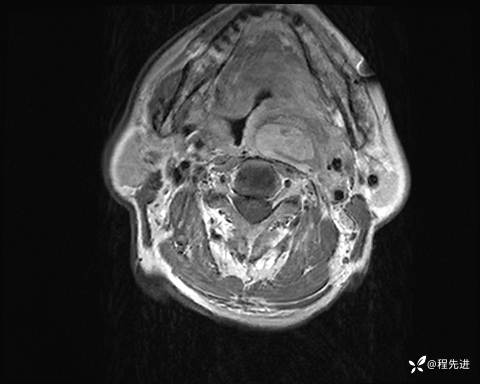

MRI平扫+增强:

T2压脂:

T1:

T1增强: